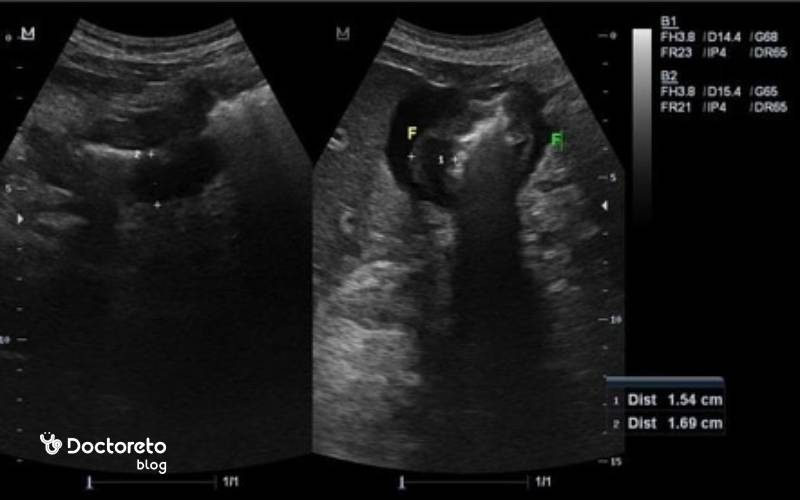

تشخیص سرطان معده با سونوگرافی

سونوگرافی یک روش غیرتهاجمی است که با استفاده از امواج صوتی، تصاویر داخل معده و اندامهای اطراف را ارائه میدهد. این روش میتواند وجود تودههای غیرطبیعی یا تغییرات در دیواره معده را نشان دهد. با این حال، سونوگرافی به تنهایی دقت کافی برای تشخیص قطعی سرطان معده را ندارد. این روش میتواند مایع آزاد شکمی، درگیری احتمالی کبد یا بزرگشدن برخی غدد لنفاوی را نشان دهد و در مواردی ضخیمشدن قابلتوجه دیواره معده را مطرح کند.

با وجود این، سونوگرافی برای دیدن مخاط معده مناسب نیست و نمیتواند ضایعات کوچک را بهطور قابل اعتماد تشخیص دهد. به همین دلیل معمولاً از آن به عنوان یک روش تکمیلی برای بررسی گسترش سرطان به کبد یا غدد لنفاوی استفاده میشود. در برخی موارد، اندوسونوگرافی (EUS) که ترکیبی از سونوگرافی و اندوسکوپی است، برای ارزیابی دقیقتر مراحل سرطان کاربرد دارد و در واقع سونوگرافی بیشتر برای بررسی مشکلات شکمی و کبدی مرتبط با سرطان معده توصیه میشود.